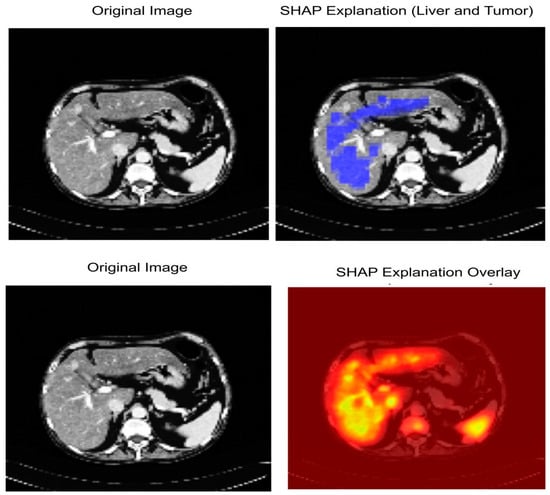

In this study, we used SHAP and Grad-CAM because they provide a more accurate pixel-level explanation, which is what we need for segmentation. In contrast to Grad-CAM’s rough heatmaps, SHAP consistently provides (theoretically motivated) explanations of how much each pixel affects the model’s prediction. Figure 11 shows explainable AI analysis.

Figure 14 shows the interpretability of our proposed model LiTs-Res-UNet + WOA with SHapley Additive exPlanations (SHAP). The first row shows the original CT image (Left) and the SHAP explanation map (Right). The blue-highlighted area represents regions identified by the model as important for the prediction of liver and tumor boundaries. The second row shows the original CT image (Left) and the SHAP overlay (Right), where the high-intensity (yellow to red) areas correspond to the pixels with higher positive SHAP values and our model is highly confident about the tumor-related characteristics. The pixels are perfectly aligned with the pathological regions identified by the radiologists, while the model’s segmentation decisions are primarily influenced by hepatic and tumorous structures, indicating the model’s understanding and focus on clinically relevant features, offering increased transparency into the model’s decision-making process via quantitative and spatial interpretation.

Figure 14.

SHAP-based Explainable AI visualization of liver and tumor segmentation.